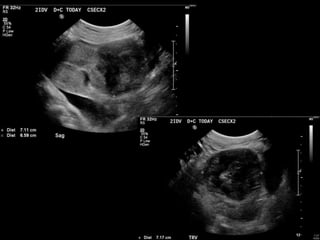

HISTORY โ€ข 40 yofemale 8.5 weeks pregant โ€ข S/P D&C for pregnancy implanted at site of c-section scar

โ€ข 6 weekspost D&C patient presents with heavy persistent bleeding โ€ข For Pelvic US โ€ข HCG = 451 mIU/mL

D&C complicated byPerforation, AVM w RPOC at Site of Perforation โ€ข AVM โ€“ Acquired or Congenital โ€ข Acquired โ€“ Traumatic โ€“ D&C, TAB, uterine surgery โ€“ Less common: Endometrial / Cervical CA, GTD โ€“ Clue on US: numerous tortuous vessels, high velocities โ€ข Tx: โ€“ transcatheter arterial embolization โ€ข Potential to preserve fertility โ€“ UA ligation, hysterectomy

POST PROCEDURE S/P embolizationof right UA and left UA due to cross collateralization

1 month followup HCG < 5 mIU/mL No flow in area โ€“ smaller in size Felt residual hematoma Will continue US follow up